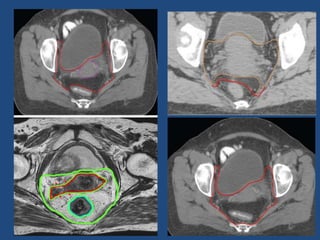

CTV Primary (CTV-P) includes GTV Primary, Uterine Cervix,

Uterine Corpus, Parametrium, Vagina and Ovaries

The uterine corpus, entire cervix and the vagina are

contoured along with the gross disease (GTV primary) as a

single structure (CTV P1)

PARAMETRIUM (CTV P2)

To delineate the parametrium , connective tissue

extending from the cervix to the pelvic wall are included, along

with the visible linear structures that run laterally (e.g. vessels,

nerves and fibrous structures)

Cranial border : defined at the level where the true pelvis begins. Contours

should stop once loops of bowel are seen next to the uterus (Lim/Toita et

al.)

Anteriorly: contouring is done up to the level of posterior border of bladder in

the central region, while, in periphery it extends till the anterior end of lateral

pelvic bony wall.

Posteriorly: parametrium is contoured only till the anterior part (semicircular)

of mesorectal fascia. In case of significant parametrial

invasion(IIIB)/uterosacral ligament involvement, include entire

mesorectum.(Lim et al.(RTOG)/PGI Guidelines).

Laterally, the parametrium is contoured till the lateral pelvic wall, upto the

medial edge of internal obturator muscle.

Caudal border of parametrium is taken at the pelvic floor.

Total CTV: CTV N and the CTV primary (CTVP1 & CTVP2) are combined and named as

total

CTV